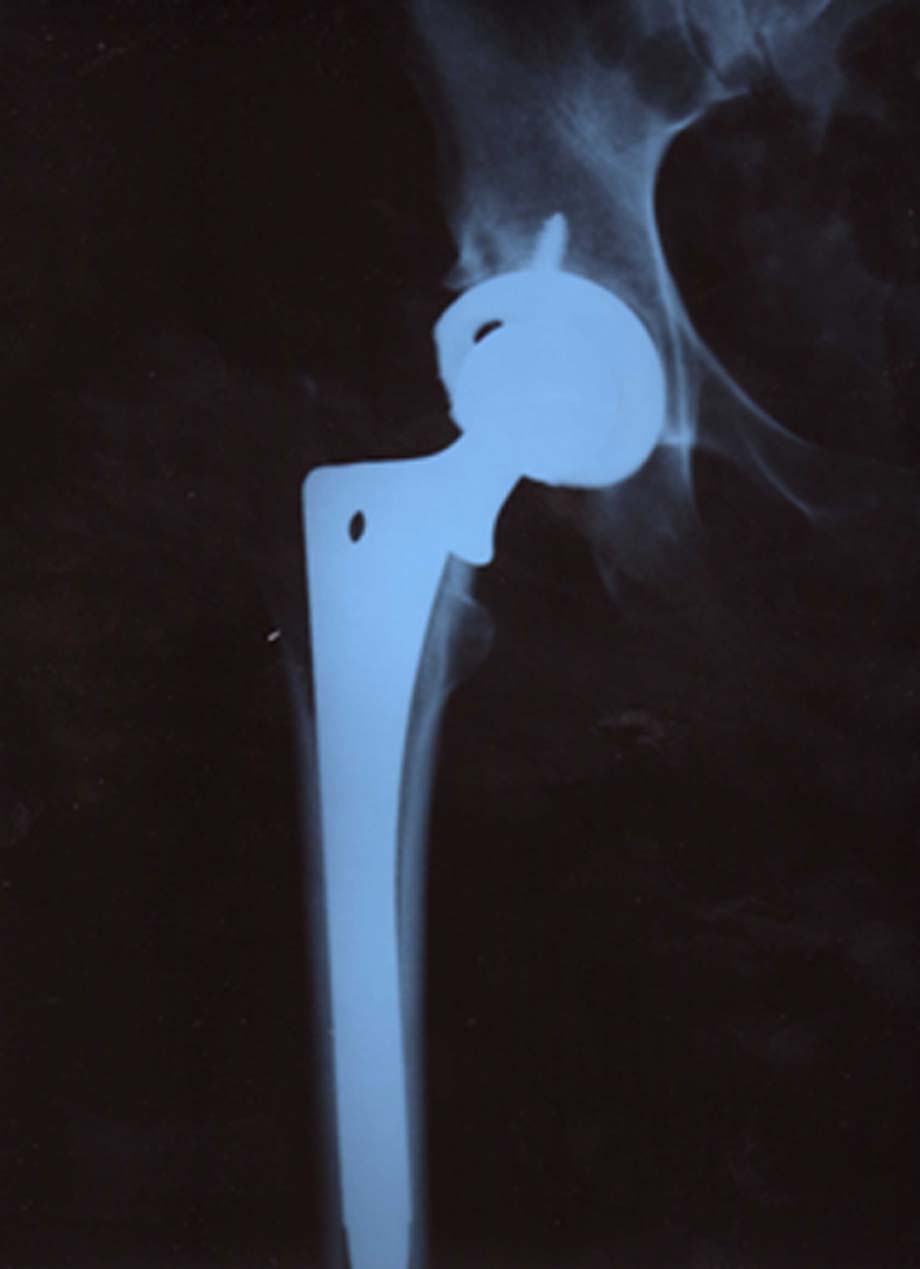

Every class needs a class clown — even Joint Replacement class at Regions Hospital in St. Paul — and I had my money on the 40-something mom who sat across the table joking quietly with her teenage daughter.We had gathered in the hospital’s cheery ninth-floor conference room — seven people facing knee or hip surgery — for a two-hour class on how to be good patients. Melinda, a nurse educator, reviewed medications and pain management. Ruby, a surgical nurse, covered pre-admission hygiene and diet. But when Lee, the last speaker, said you face weeks of exercise and physical therapy after a hip replacement, the mom erupted:”I might as well keep the old one!” she said.